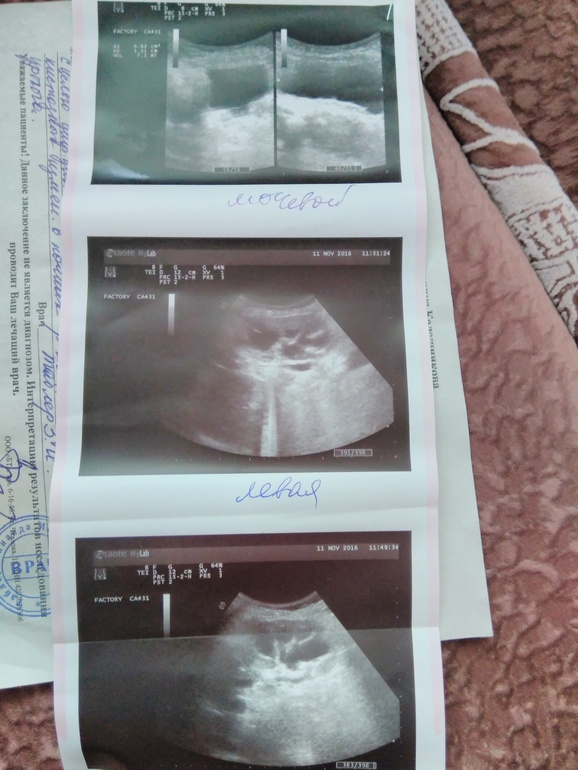

Ну а размеры почек нормальные?что вы можете сказать по фотографиям узи есть ли кисты?а то по другому узи нам поставили множественные кисты.прям и не знаю кому верить.

Я бы вообще переделал УЗИ, прежде чем что то комментировать. По фотографиям фотографий крайне сложно что то понять. Диагноза у вас пока никакого нет, его ставит не врач УЗИ, а клинический доктор